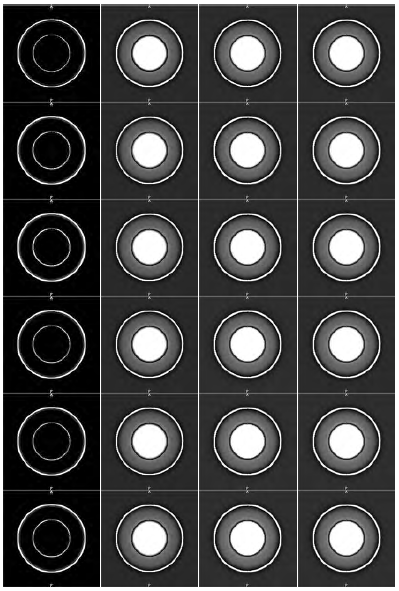

The dataset is constructed in order to simulate the endocardium and the left ventricle wall by means an internal cone and an external cone, respectively. In three-dimensional space, the computer generated cardiac phantom is shown as two truncated cones, inner and outer. The synthetic image size is 256 × 256 × 50, and it is quantized signed to 12-bit. The dimensión of the axial plane is set to 256 × 256 because in this two-dimensional region the left ventricle in a normal CT cardiac scan is located. Moreover, 50 CT slices are considered because that amount represents 20% of a cardiac scan, which is the region size normally scanned for the left ventricle. Figure 1 shows the synthetic image. The axial view at slice 25 is shown in Figure 1.a meanwhile Figure 1.b shows the coronals views at planes 141 and 182 respectively. The image is corrupted with noise using the algorithm proposed in[25].

Figure 2 shows the twenty-four images generated from the each combination of cases-neighborhood space. Figure 2 can be explored as a matrix with the following characteristics, each column represents each case main, residual1, residual2 or full, while each row represents a neighborhood space. The first row represents the neighborhood space for n = 1, the other rows for n = 2, 3, 4, 5, 6. Through the visual inspection of images in Figure 2, it has been demonstrated the effectiveness of the similarity enhancement filter in improving the quality of images corrupted with noise and artifacts.

The improvement is specifically obtained for cases 2-4 (residual1, residual2 and full) which correspond to the images shown in columns 2, 3 and 4 of the Figure 2. In column 1 of the Figure 2, the results associated with case 1 (main) can be observed, in this case, the filter behaves as an edge detector.

The analysis of the results obtained from synthetic data by visual inspection is based on the hypothesis that an image with sharp or enhanced edges is usually more pleasing subjectively than the original image. When the images enhanced are displayed on a high-resolution monitor, some qualitative criteria such as a general quality, sharpness, contrast, and noisiness can be evaluated. Each component of the similarity criterion is analyzed according to these qualitative criteria. Two remarks are appropriate for experiment with synthetic images (section 3.1).

First, the component main behaves as an edge detector operator since this component does not improve the subtle details present in uniform regions of the image. Thus, the component main derives the spatial structure of the image when the high frequency details are emphasized. Second, the components residual1, residual2 and full allow enhancing all information in the original image. The image contrast is high, the objects edges are sharp and there is no noisy appearance. From the Figure 2, it is verified that the enhancement achieved using the component full generates the wider edges.